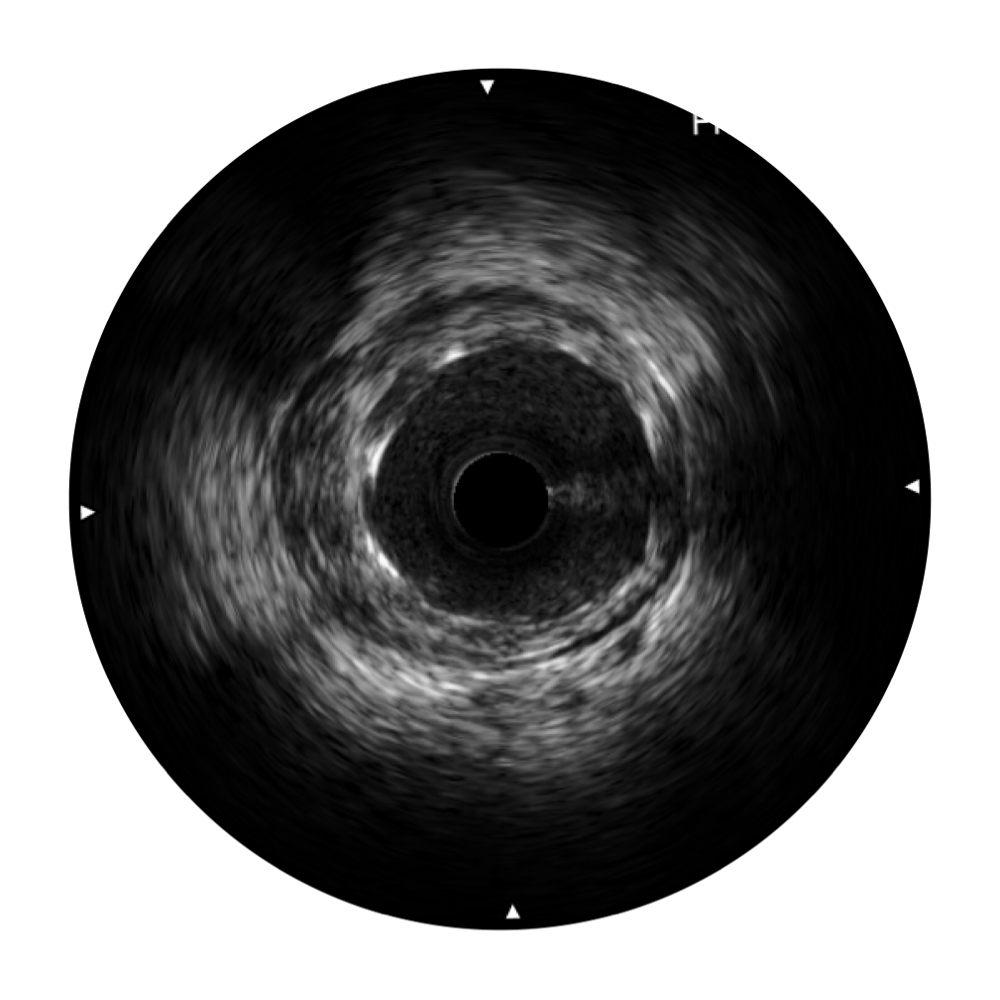

九州酷游宽频IVUS图像

对比传统IVUS导管成像,九州酷游宽频IVUS图像的近场支架梁显影更细腻,远场中膜外血管仍清晰可辨,兼顾远中近,兼顾分辨力与穿透深度